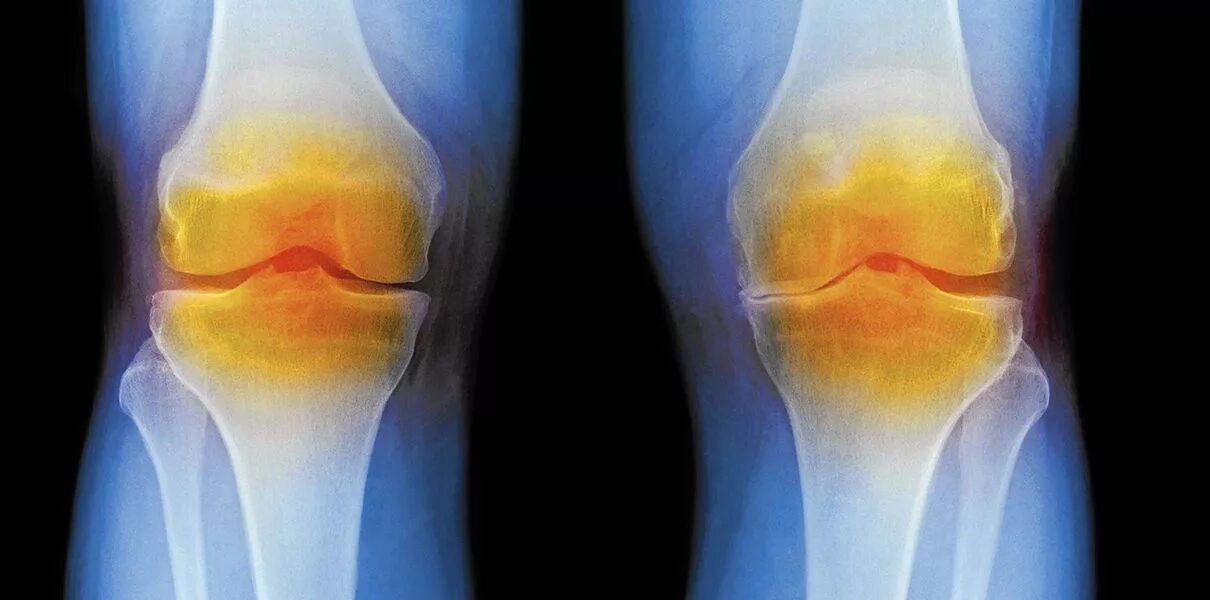

Повреждение мягких тканей суставов костей